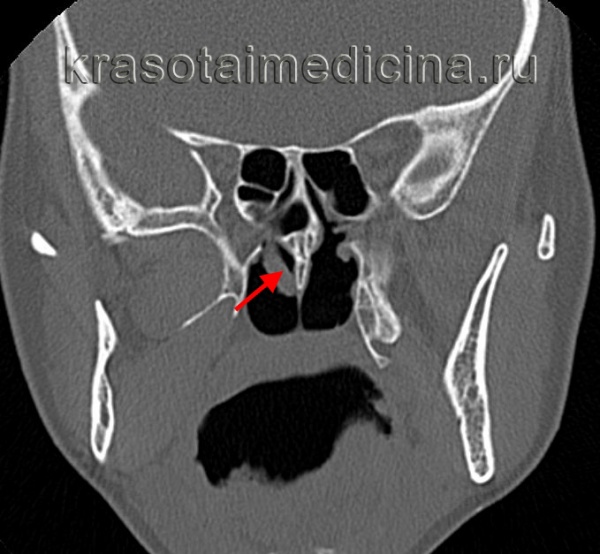

(Слева) При корональной «костной» КТ определяется снижение пневматизации левой верхнечелюстной пазухи, устье которой расширено. Визуализируется большой одиночный полип, пролабирующий через устье в полость носа и приводящий к обструкции среднего носового хода.